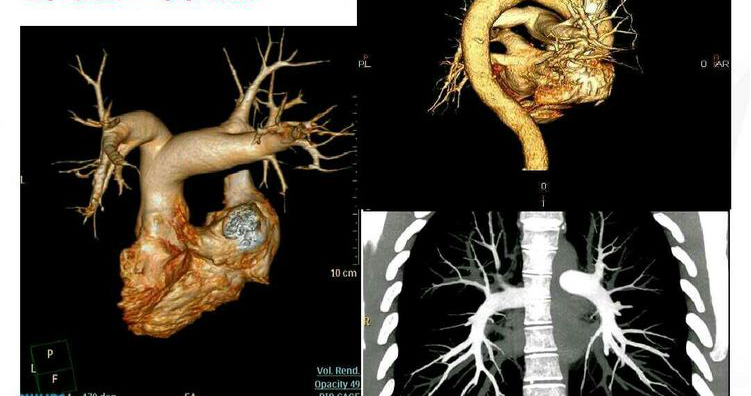

五.CT血管造影(CTA)

128层螺旋CT 血管成像技术是一种比较可靠、简便、经济而且安全的血管病变无创检查手段。可以很好的显示动脉血管的解剖变异,能够正确诊断动脉血管不同程度的狭窄,诊断重度以上的狭窄的敏感性与特异性均较高,CTA诊断血管闭塞的敏感性和特异性达到100%。

胸腹主动脉CTA

主动脉成像

任意方向的二维断面图像可更好地显示正常结构及病变的完整性,三维重建图像对病变的诊断及治疗方案的设计价值极大。

128层CT最擅长的是心、肺、血管方面的检查,能让临床医生看到更多的细节,它可以将病变的血管“拉”出来观察,还可以“剥皮、去骨”,小到0.5毫米的病变都能让医生一目了然。可用于筛查冠心病、肺癌、肝硬化,并进行良性与恶性肿瘤的分析,有利于早发现、早诊断、早治疗,真正是患者的福音,医生的良友。